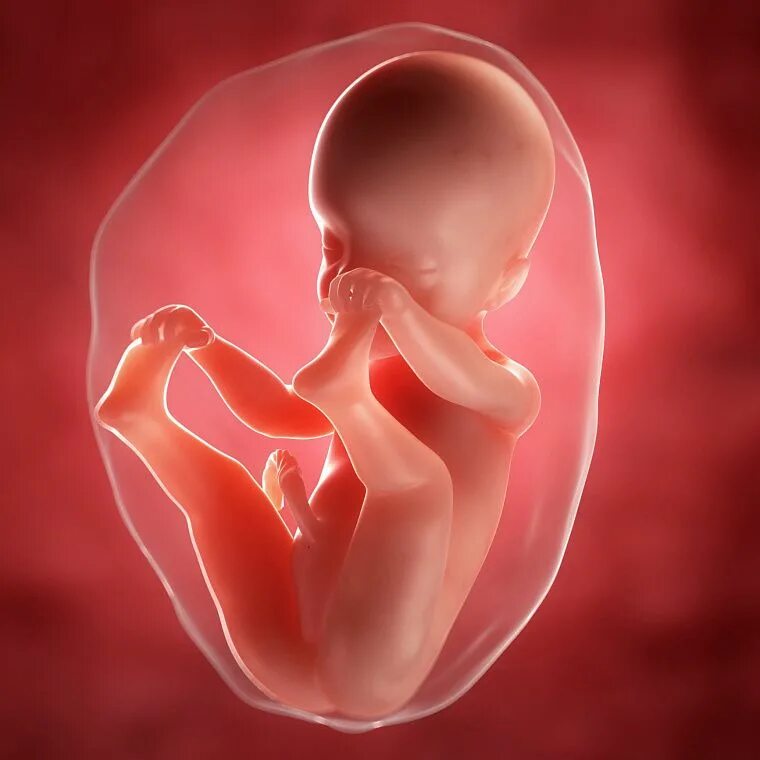

Ощущения 27 неделя